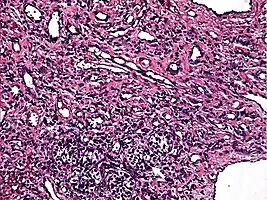

Low power photomicrograph of an endovascular papillary angioendothelioma showing papillae with hyalinized cores -

High power view showing a vascular tumor with cuboidal endothelium lining the vessels. Few entrapped seminiferous tubules are also noted (arrow). -

Characteristic budding, hobnail-like endothelial cells visible.